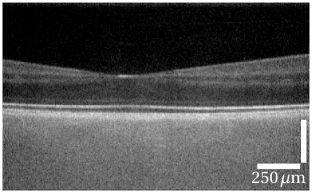

Using the high speed CMOS camera human retina was measured in vivo at million A-scans/s with off-axis reference (Fig. 5a, c, e). To enhance the imaging quality, which was compromised by the low signal level at the high imaging speed, volumetric data sets of OCT images were cross-correlated, shifted accordingly in all three dimensions, and averaged (Fig. 5b, d, f).

Given the acquisition speed, which was at significalty faster than that of commercially available OCT devices, image quality of the full-field system is remarkable. All retinal layers that are usually visible in OCT imaging can be clearly distinguished (see Fig. 5g). Intensities of the different layers above the RPE differ only slightly between FF-SS-OCT and scanned OCT. Below the RPE the choroid shows high signal intensities, but hardly any structures. Here mostly multiple scattered photons were detected due to the lack of a confocal gating. Photons from the strongly scattering RPE [23] or choroid are always assigned to depths higher than the depth of any of their scattering events and thus below the RPE. Therefore they disturb imaging of the choroid, but do not corrupt imaging of the neuronal layers.